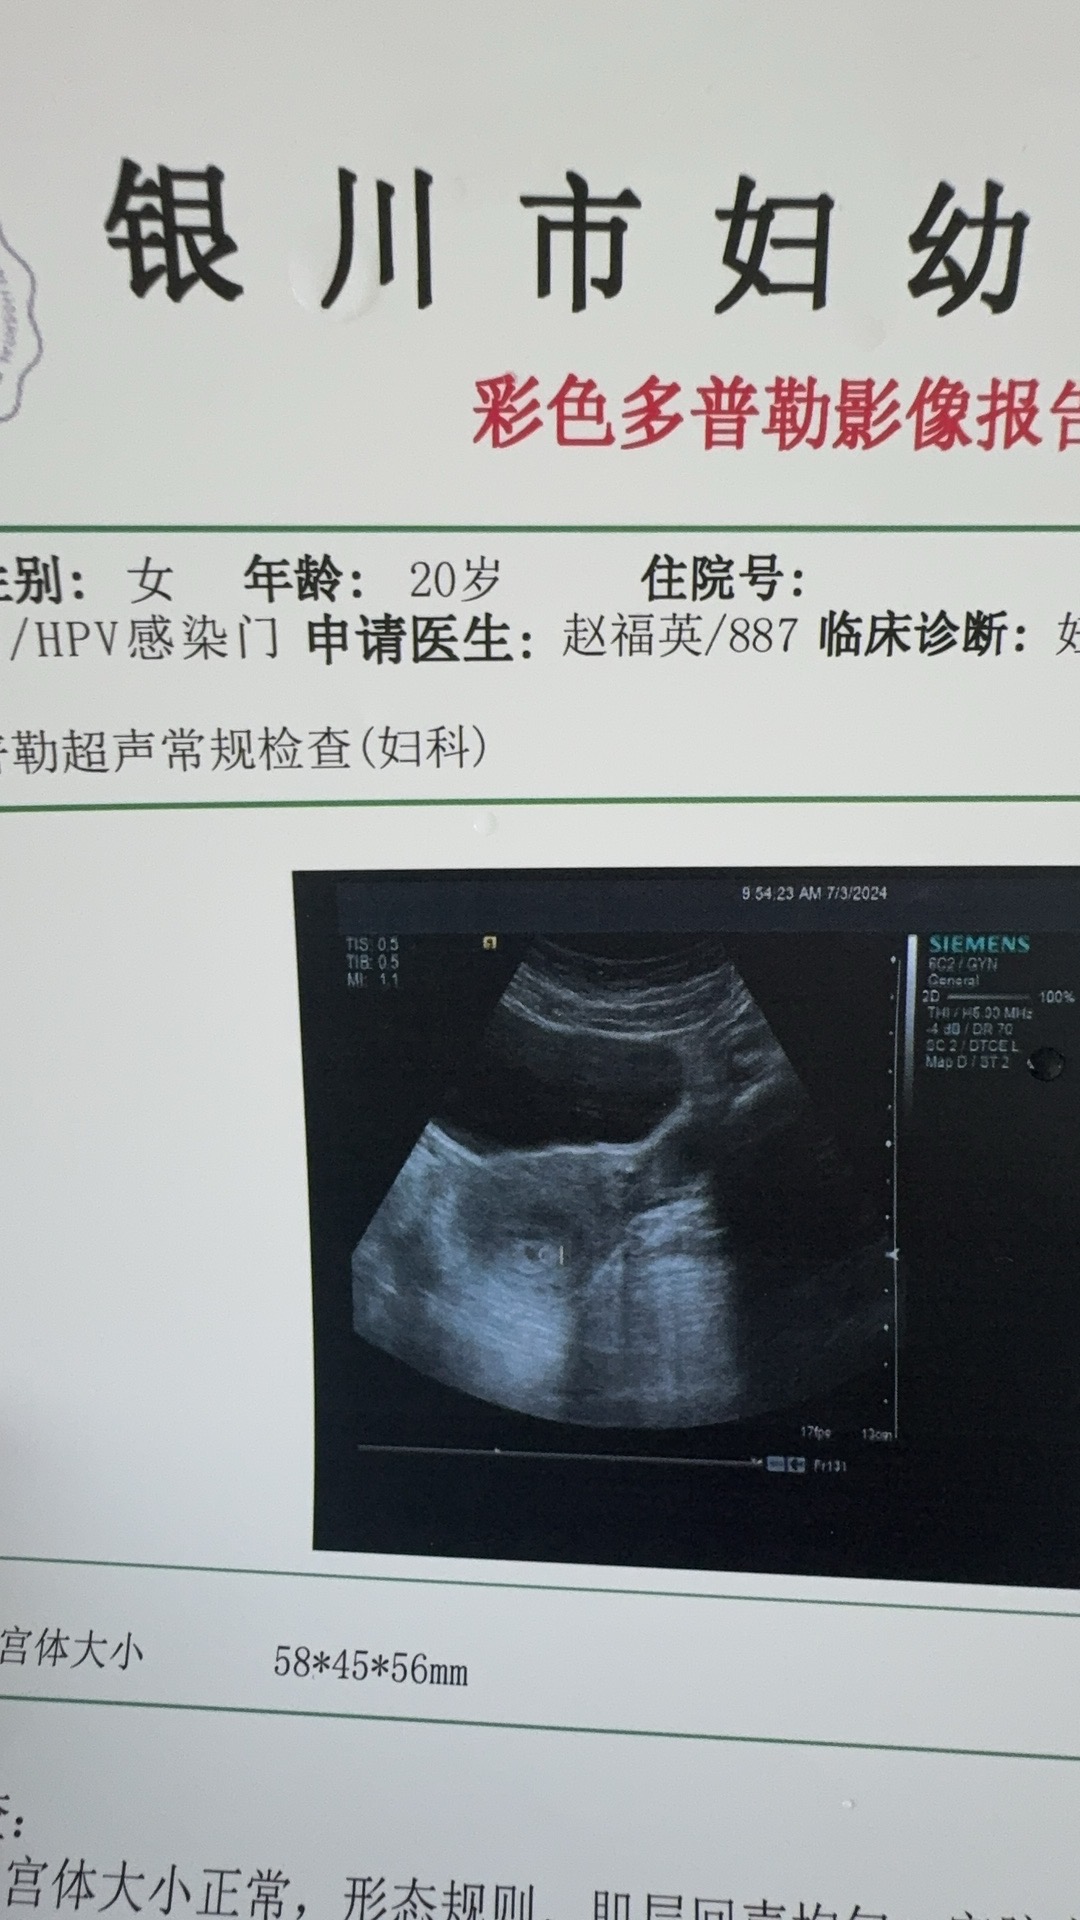

你发上来的B超图片不清晰,只是看到宫腔内小暗区,如果你平时月经周期规律,粗略估计目前是5周左右大小

您好,如果月经规律,怀孕天数从末次月经第一天算起。如果月经不规律,可以根据血HCg和超声监测的胎芽大小估算怀孕的天数。做试管的,要根据移植胚胎的时间和移植的第几天胚胎推算怀孕天数。您的这个超声只是提示宫内有个小暗区,未见胎心台呀,不好估算明确的怀孕时间。

你好,宫腔内能看到液性暗区至少有五周了

左侧小腹隐痛需要进一步检查排除异位妊娠